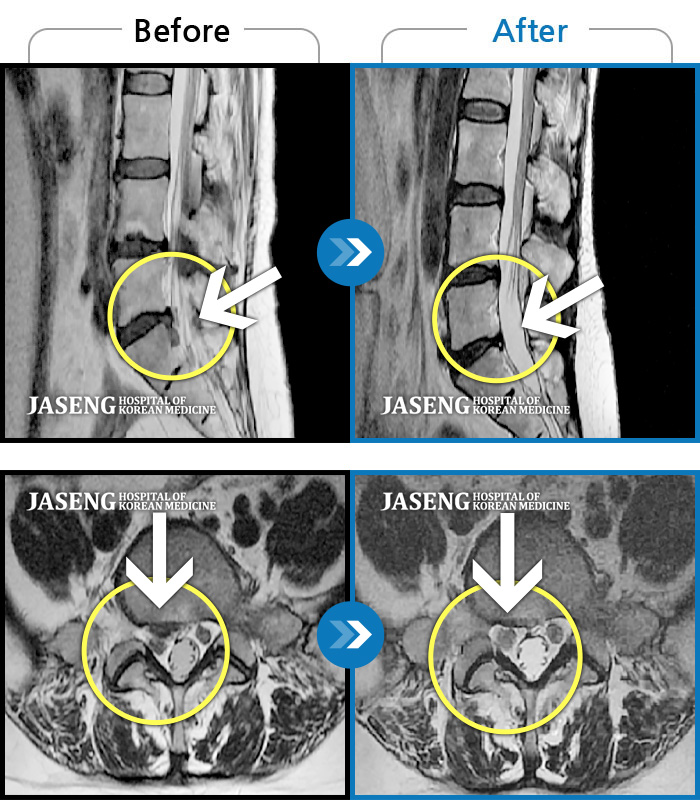

김상돈 원장님 칭찬 드립니다 대학병원,척주질환 전문 병원에서 목디스크 수술 진단을 받았었는데 지인 추천으로 자생한방병원을 방문 했었는데 김상돈 원장님께서 친절한 설명과 성심성의 치료를 해주신 덕분에 일상 생활을 정상 적으로 하고 있습니다 원장님 감사합니다